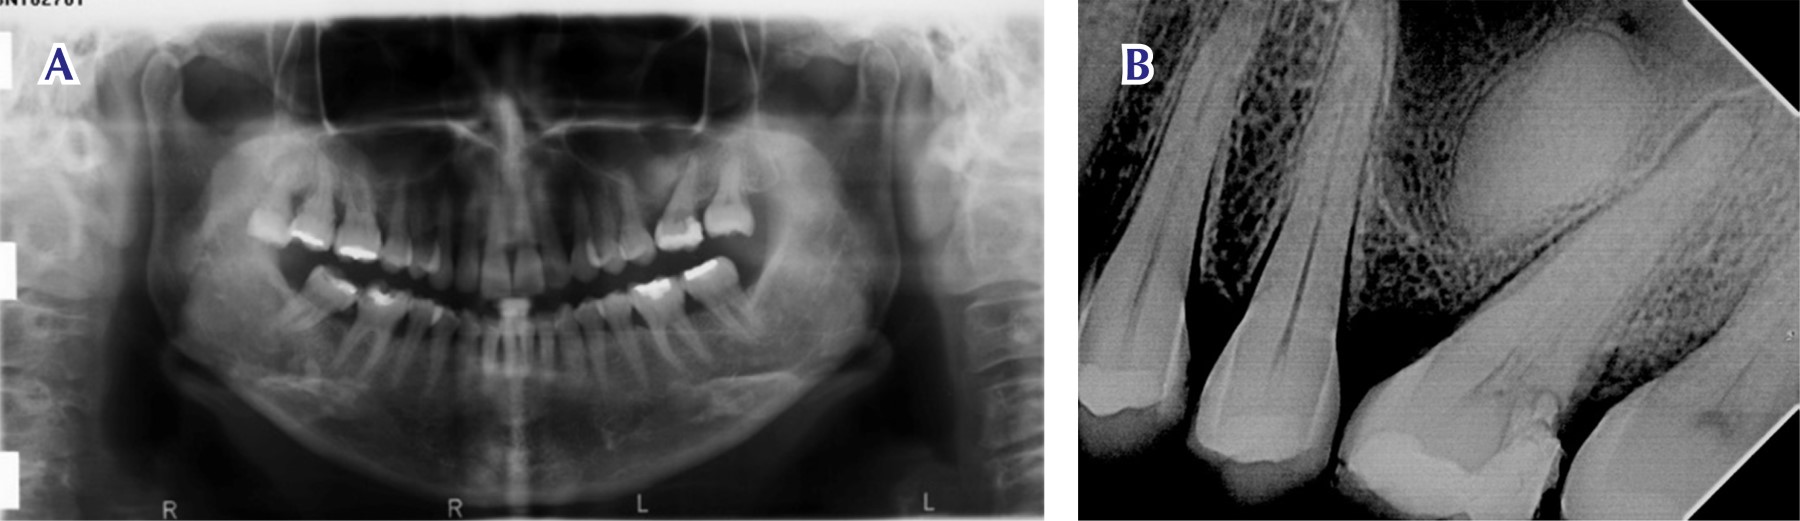

Figure 1